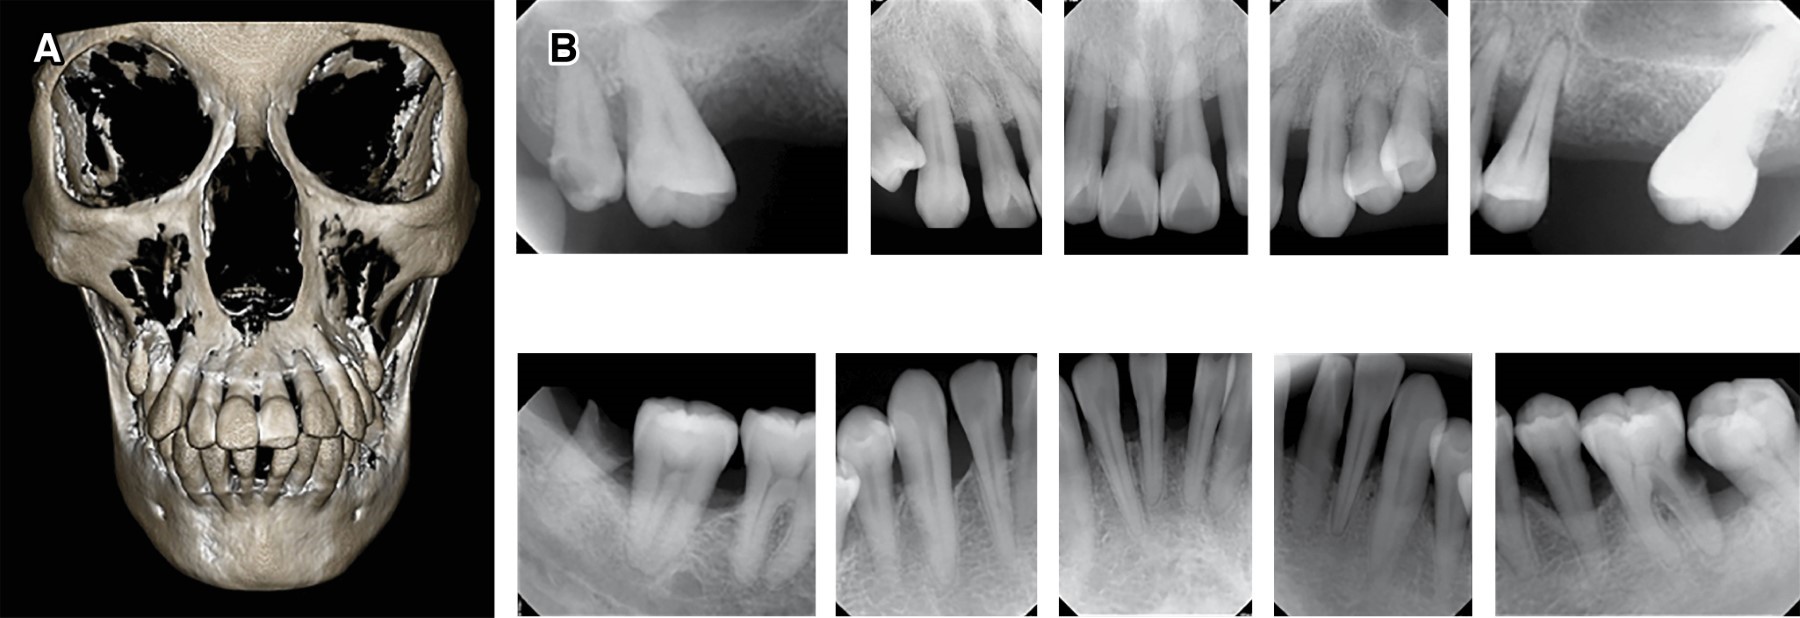

Figure 3